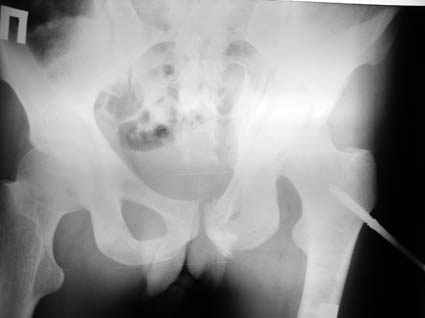

Все-таки надо бы начать не с КТ, а с обзорного снимка таза и косых проекций впадины.

Это обзорные и косые снимки

С уважением,

Привет, Леонид. Оскольчатый высокий двухколонный перелом в такие сроки трогать не надо, т.к. это про такие переломы сказано: "кто с ножом на Ж. пойдет тот в ней и останется...".